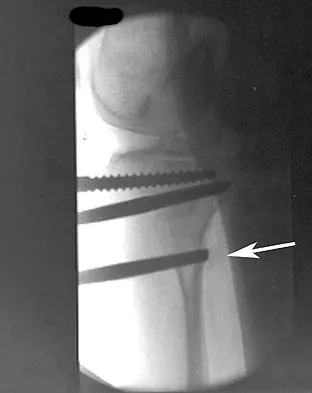

Question 99 High Yield

In performing an opening wedge high tibial osteotomy at the tibial tubercle, the osteotome extends 5 mm posteriorly and centrally out of the bone as shown in Figures 17a and 17b. What is the first structure it enters?

Detailed Explanation